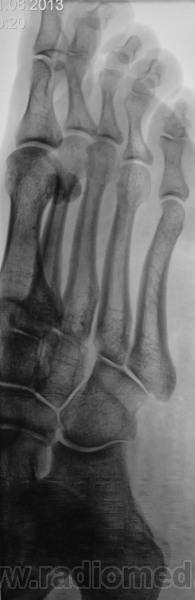

Пол пациента: Женский пол Тип патологии: Травма Область исследования: Скелетно-мышечная система Методы исследования: Rg Травма. Направлена на рентгенографию стопы https://radiomed.ru/sites/default/files/styles/case_slider_image/public/user/12/2.201201010002.jpg?itok=qphoJ66e ID:30984 Wed, 21/08/2013 - 21:56 #1 Катенёв Валенти... Offline Last seen: 7 years 2 months ago Joined: 22.03.2008 - 22:15 Posts: 54876 ЧЁ, норму писать? Wed, 21/08/2013 - 22:12 #2 Сергей Кузьминов Offline Last seen: 1 year 2 months ago Joined: 06.10.2012 - 15:51 Posts: 11813 Не узрел патологии. Wed, 21/08/2013 - 22:13 #3 Катенёв Валенти... Offline Last seen: 7 years 2 months ago Joined: 22.03.2008 - 22:15 Posts: 54876 Сергей Кузьминов wrote: Не узрел патологии. Приложения: Wed, 21/08/2013 - 22:17 #4 Сергей Кузьминов Offline Last seen: 1 year 2 months ago Joined: 06.10.2012 - 15:51 Posts: 11813 Опаньки,перелом. Thu, 22/08/2013 - 07:05 #5 Глазков Игорь А... Offline Last seen: 11 months 1 day ago Joined: 19.12.2008 - 20:41 Posts: 1597 всегда должны быть на вооружении. Я тоже не увидел вначале перелома. Прийди к Себе Thu, 22/08/2013 - 22:14 #6 Катенёв Валенти... Offline Last seen: 7 years 2 months ago Joined: 22.03.2008 - 22:15 Posts: 54876 Это "матушка" - жена "батюшки" из одного довольно большого села нашего района. Просто ударилась мизинцем об ножку стула.

Опаньки,перелом.

всегда должны быть на вооружении. Я тоже не увидел вначале перелома.

Это "матушка" - жена "батюшки" из одного довольно большого села нашего района.

Просто ударилась мизинцем об ножку стула.